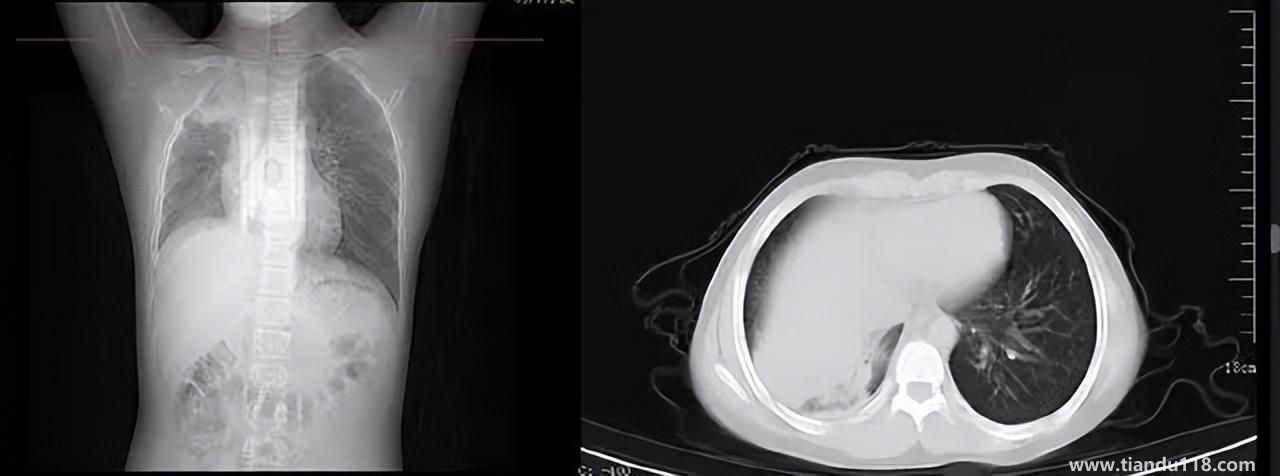

3個(gè)辦法可提前預(yù)警白肺(咋預(yù)防“白肺”) 3個(gè)辦法可提前預(yù)警白肺(咋預(yù)防“白肺”)家里有老人,擔(dān)心出現(xiàn)“大白肺”、“沉默型缺氧”等情況,具體如何應(yīng)對(duì),提前預(yù)警?近日,大象新聞接到諸多咨詢。針對(duì)這些問題,大象新聞?dòng)浾咦隽硕喾讲稍L。什么是白肺?對(duì)... 小編 2022-12-28 693

男孩咳嗽發(fā)熱在家硬扛成白肺(醫(yī)生表示以下幾種情況別硬“扛”) 男孩咳嗽發(fā)熱在家硬扛成白肺(醫(yī)生表示以下幾種情況別硬“扛”) 近日,一名12歲男孩咳嗽一周不就醫(yī),一側(cè)肺部“扛”成了“白肺”?!氨е鴥e幸心理一直在家硬‘扛’,沒想到‘扛’出這么重的病!”孩子家長悔不... 小編 2022-12-28 939

為何有人出現(xiàn)“白肺”?專家回應(yīng)和疫苗接種無關(guān) 為何有人出現(xiàn)“白肺”?專家回應(yīng)和疫苗接種無關(guān)國務(wù)院聯(lián)防聯(lián)控機(jī)制12月27日召開新聞發(fā)布會(huì),針對(duì)有媒體提問稱,從近期公眾的反映情況看,有的新冠病毒感染者在就診過程中發(fā)現(xiàn)了肺炎或者是CT出現(xiàn)了“白肺”的現(xiàn)... 小編 2022-12-27 817

感染新冠會(huì)變白肺?醫(yī)生:有年輕病例 感染新冠會(huì)變白肺?醫(yī)生:有年輕病例感染新冠會(huì)變白肺嗎?對(duì)此,有專家表示,造成“白肺”情況有很多種,感染新冠只是一種可能。少量患者肺有滲液 ,咳嗽不會(huì)引發(fā)白肺,有年輕人病例。... 小編 2022-12-27 608